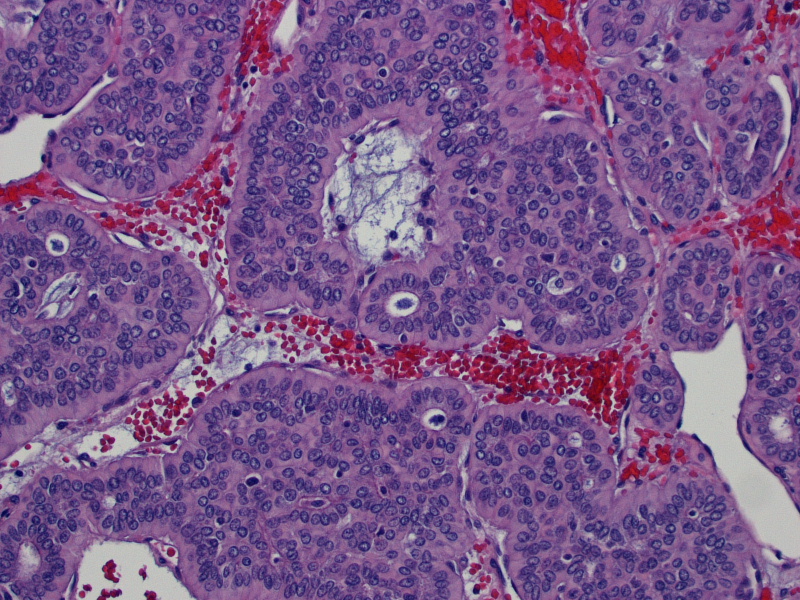

PLEOMORPHIC ADENOMA Histopathology.guru Malignant Pleomorphic Adenoma Pathology Outlines Benign adnexal tumor of the skin composed of mesenchymal and sweat gland components. Pleomorphic adenoma (pa) is the most common salivary gland neoplasm, and its diagnosis is straightforward in the majority of cases. Pleomorphic adenomas are benign ‘mixed’ tumors that consist of varying proportions of epithelial and mesenchymal elements. Malignant cases arising from pleomorphic adenoma (am j clin pathol 2011;136:793). Malignant Pleomorphic Adenoma Pathology Outlines.